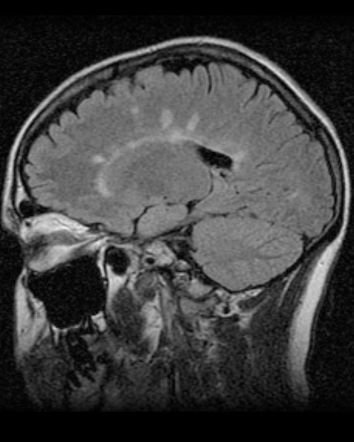

La TC es muy útil para el diagnóstico de la esclerosis múltiple, V/F:

Falso, es la RM

Se pueden apreciar _______ en T2 y FLAIR.

• Hiperintensidades calloseptales

¿Qué hallazgos en RM se pueden encontrar en la esclerosis múltiple,?

• Pequeñas (5 a 10 mm), lineales y ovoides

• Dedos de Dawson

• Periventriculares